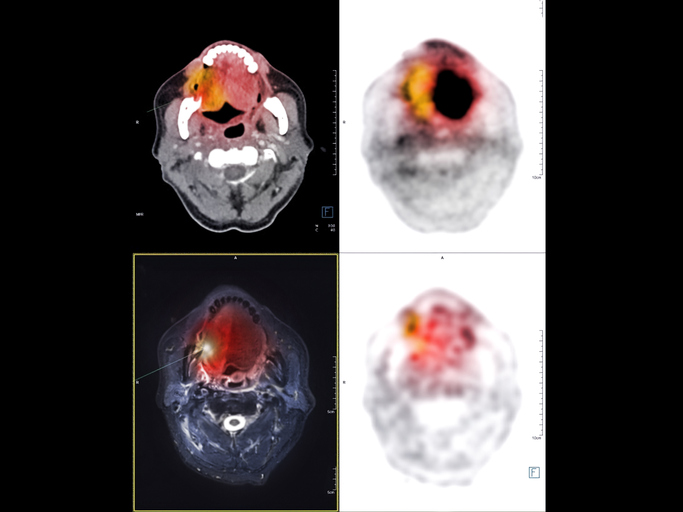

41nfEKnow2L._AC_SY200_QL15_.jpg。はじめましてのPET/CT | 村上 康二, 鳥井原 彰, 岩渕 雄 |本。はじめましてのPET/CT | 村上 康二, 鳥井原 彰, 岩渕 雄 |本。PETとCTの基礎から応用までを解説した専門書。総合内科病棟マニュアル 2冊セット。お値下げ交渉は致しません。GettyImages-1312085414.jpg。- タイトル: はじめましてのPET CT- 出版社: メディカルビュー社- ISBN: 9784758321150- 価格: 7700円こちらは裁断済みです。裁断済みの意味がわかる方のみご購入をお願いします。眼科のいろは IROHAシリーズDVD Vol.1。イラストレイテッド生理学。#Clinical Neuroscience #クリニカルニューロサイエンス#神経内科#脳神経外科#脳神経内科#放射線科#画像診断